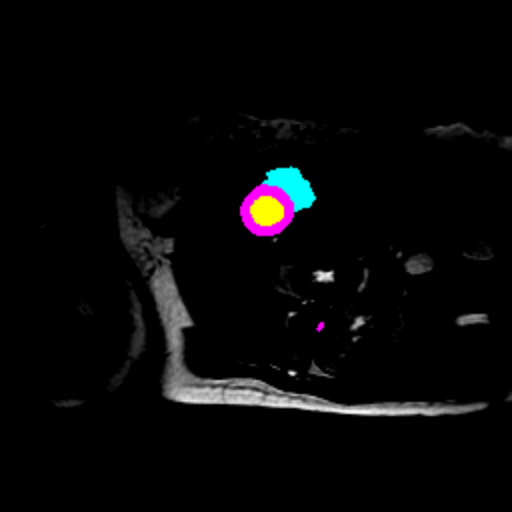

Figure 3 presents a qualitative comparison of segmentation performance on examples from the Synapse, BTCV, ACDC, and ISIC17 datasets. The first two examples (from Synapse) highlight variations in segmentation performance among U-Net, TransUnet, Mamba-Unet, and Swin-Unet. While Swin-Unet performs well in the first example, its performance decreases in the second example, particularly in segmenting the organ highlighted in blue. Additionally, it misclassifies background regions as the class highlighted in orange. In contrast, our approach demonstrates high robustness in segmenting all classes accurately and aligning well with the ground truth masks.

Across BTCV, ACDC, and ISIC17, the comparison methods exhibit varying performance depending on the task and class. For instance, Mamba-Unet struggles to segment multiple organs in BTCV, even misclassifying certain classes as others. In the ACDC dataset, both TransUnet and Mamba-Unet perform poorly in segmenting the three classes. In the last column (ISIC17), Swin-Unet oversegments the skin lesion compared to the ground truth. Unlike the comparison models, our approach consistently delivers effective segmentation across different tasks and datasets.

These qualitative findings further reinforce the quantitative results presented in the experimental section, demonstrating the effectiveness of our MambaCAFU model in handling binary and multi-class segmentation across diverse medical imaging modalities and tasks.

Slice GT Unet TransUnet Mamba-Unet Swin-UMamba MambaCAFU-V1

Figure 3: Visual comparison of segmentation examples from Synapse (first two examples), BTCV (3-4 examples), ACDC (5th example) and ISIC17 (last example). Columns: input slice, ground truth, Unet, TransUnet, Mamba-Unet, Swin-UMamba, and MambaCAFU-V1.